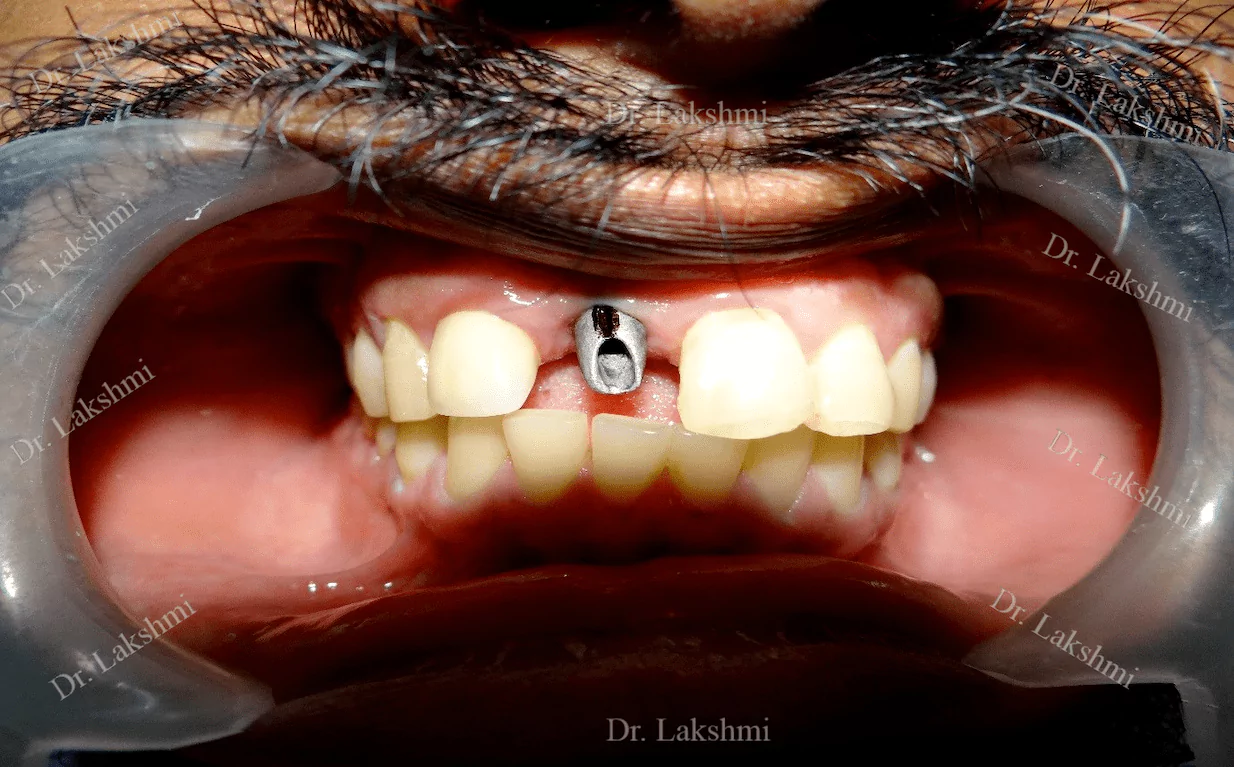

Requires the placement of a single dental implant (either 2 stage or 1 stage) in the region of the missing tooth, followed by a crown (artificial tooth) over

Treatment Duration: 2 stage dental implants: The replacement is completed in 2 stages which are spread over an interval of minimum 3 months. The first stage involves the placement of the implant and requires one to two sittings,Temporary Crowns will be given to the patient. The second stage involves the placement of the artificial tooth (Permanent crown).

1 stage dental implant: Requires just one stage for the placement of the implant and crown(Permanent Crown).